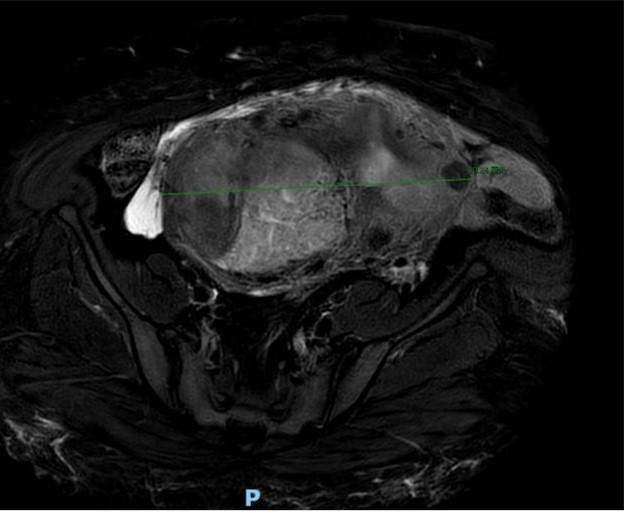

近日,我院子宫肿瘤一病区主任李大鹏团队利用达芬奇机器人手术系统,成功为一名极度肥胖患者实施达芬奇机器人辅助全子宫切除+双侧附件切除术,顺利切除20cm巨大子宫肌瘤。该手术的成功实施,再次体现了机器人手术在复杂妇科疾病、尤其是极度肥胖患者中的独特优势。

患者女性,身高156cm,体重145kg,BMI高达59.6,属于极度肥胖体型。患者合并贫血、支气管哮喘、心肺功能欠佳等多种慢性病,同时存在盆腔粘连、骨盆狭窄等情况,下腹壁脂肪层极厚,不仅增加麻醉与围手术期风险,也为手术操作带来了极大困难。该患者子宫及肿瘤横径超20cm,占据整个盆腔,下腹壁脂肪堆积腹壁厚度超过10cm。患者先后就诊于省内多家医院均未能手术,遂转诊我院。

严格无瘤操作,装袋小切口取瘤